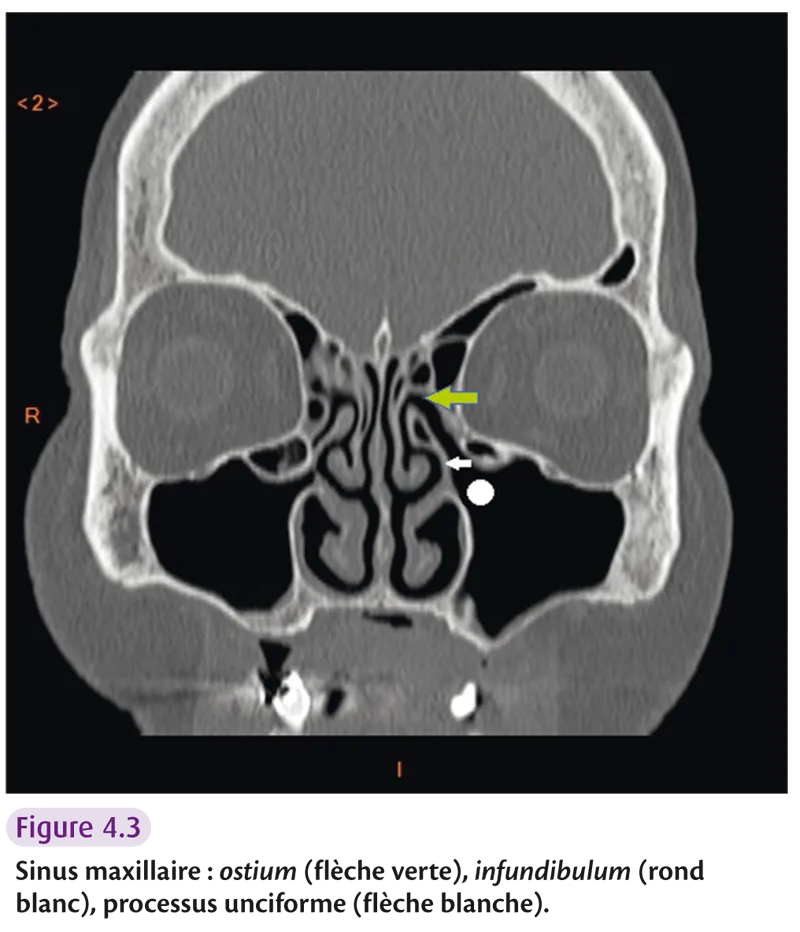

Sinus maxillaire

Il réalise une vaste cavité creusant l’os maxillaire (figure 4.3). Le cornet inférieur divise la face mésiale en deux segments : supérieur (répondant au méat moyen) et inférieur (où s’ouvre le canal lacrymonasal). On retrouve le foramen infraorbitaire (passage du nerf infraorbitaire branche du V2) dans la paroi supérieure du sinus maxillaire.

Fig 4.3

L’anatomie radiologique comprend les trois cornets (inférieur, moyen et supérieur) et le vomer, os impair et médian participant à la constitution du septum nasal. Deux gouttières sont également décrites : l’infundibulum, extension supéro-interne de l’ostium du sinus maxillaire et le canal nasofrontal (figure 4.5). Ces gouttières s’ouvrent dans la gouttière uncibullaire (hiatus semi-lunaire) et rejoignent la gouttière rétrobullaire (sinus lateralis).